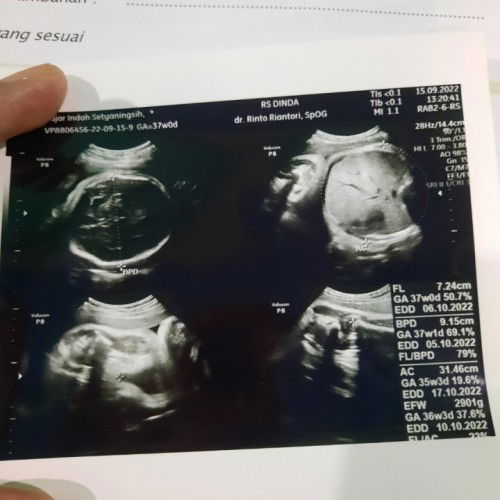

Bund mau tanya dong aku hamil anak kedua uk 37weeks, tadi siang usg kata dokter kepala sudah dibawah tapi belum masuk panggul dan air ketuban sedikit. Setiap hari saya sudah sering jalan kaki antar jemput anak sekolah padahal🥲 Kira² bisa lahiran normal nggk ya?#seriusnanya #firstmom #pleasehelp